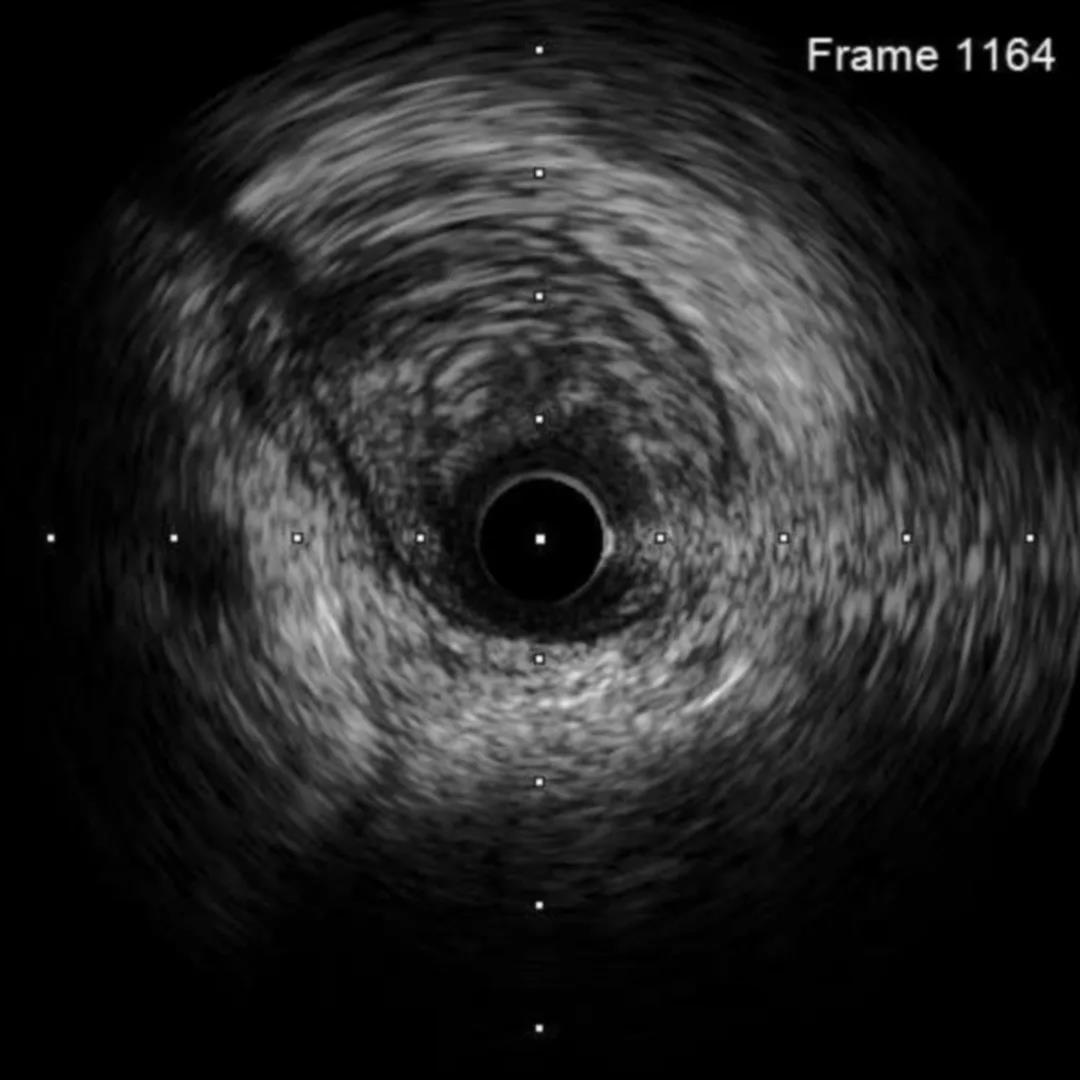

IVUS-1

远段直径2.2*2.4mm

对角支处局限血肿